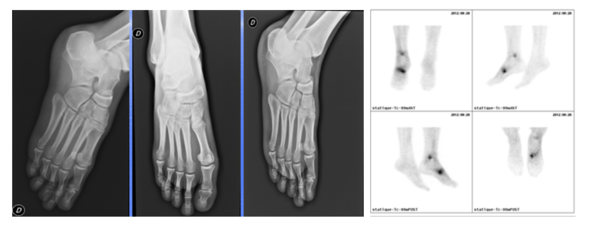

L’indication la plus probante du SPECT/CT en pathologie ostéo-articulaire bénigne est la douleur post-traumatique persistante malgré une radiographie standard négative(1). La technique permet en effet de dépister avec une très grande sensibilité, ou a contrario d’exclure formellement, une lésion osseuse fracturaire, avec ou sans déplacement. Les figures 3a à 3d illustrent parfaitement cette indication dans le cas d’un patient sportif s’étant présenté pour douleurs post-traumatiques et chez qui la radiographie standard se révélait normale, au contraire du SPECT-CT qui mettait en évidence deux fractures, tibiale distale et métatarsienne (fig. 3c et 3d).

Figure 3a à gauche - Radiographies normales suite à un trauma sportif

Figure 3b à droite - Scintigraphie planaire pathologique